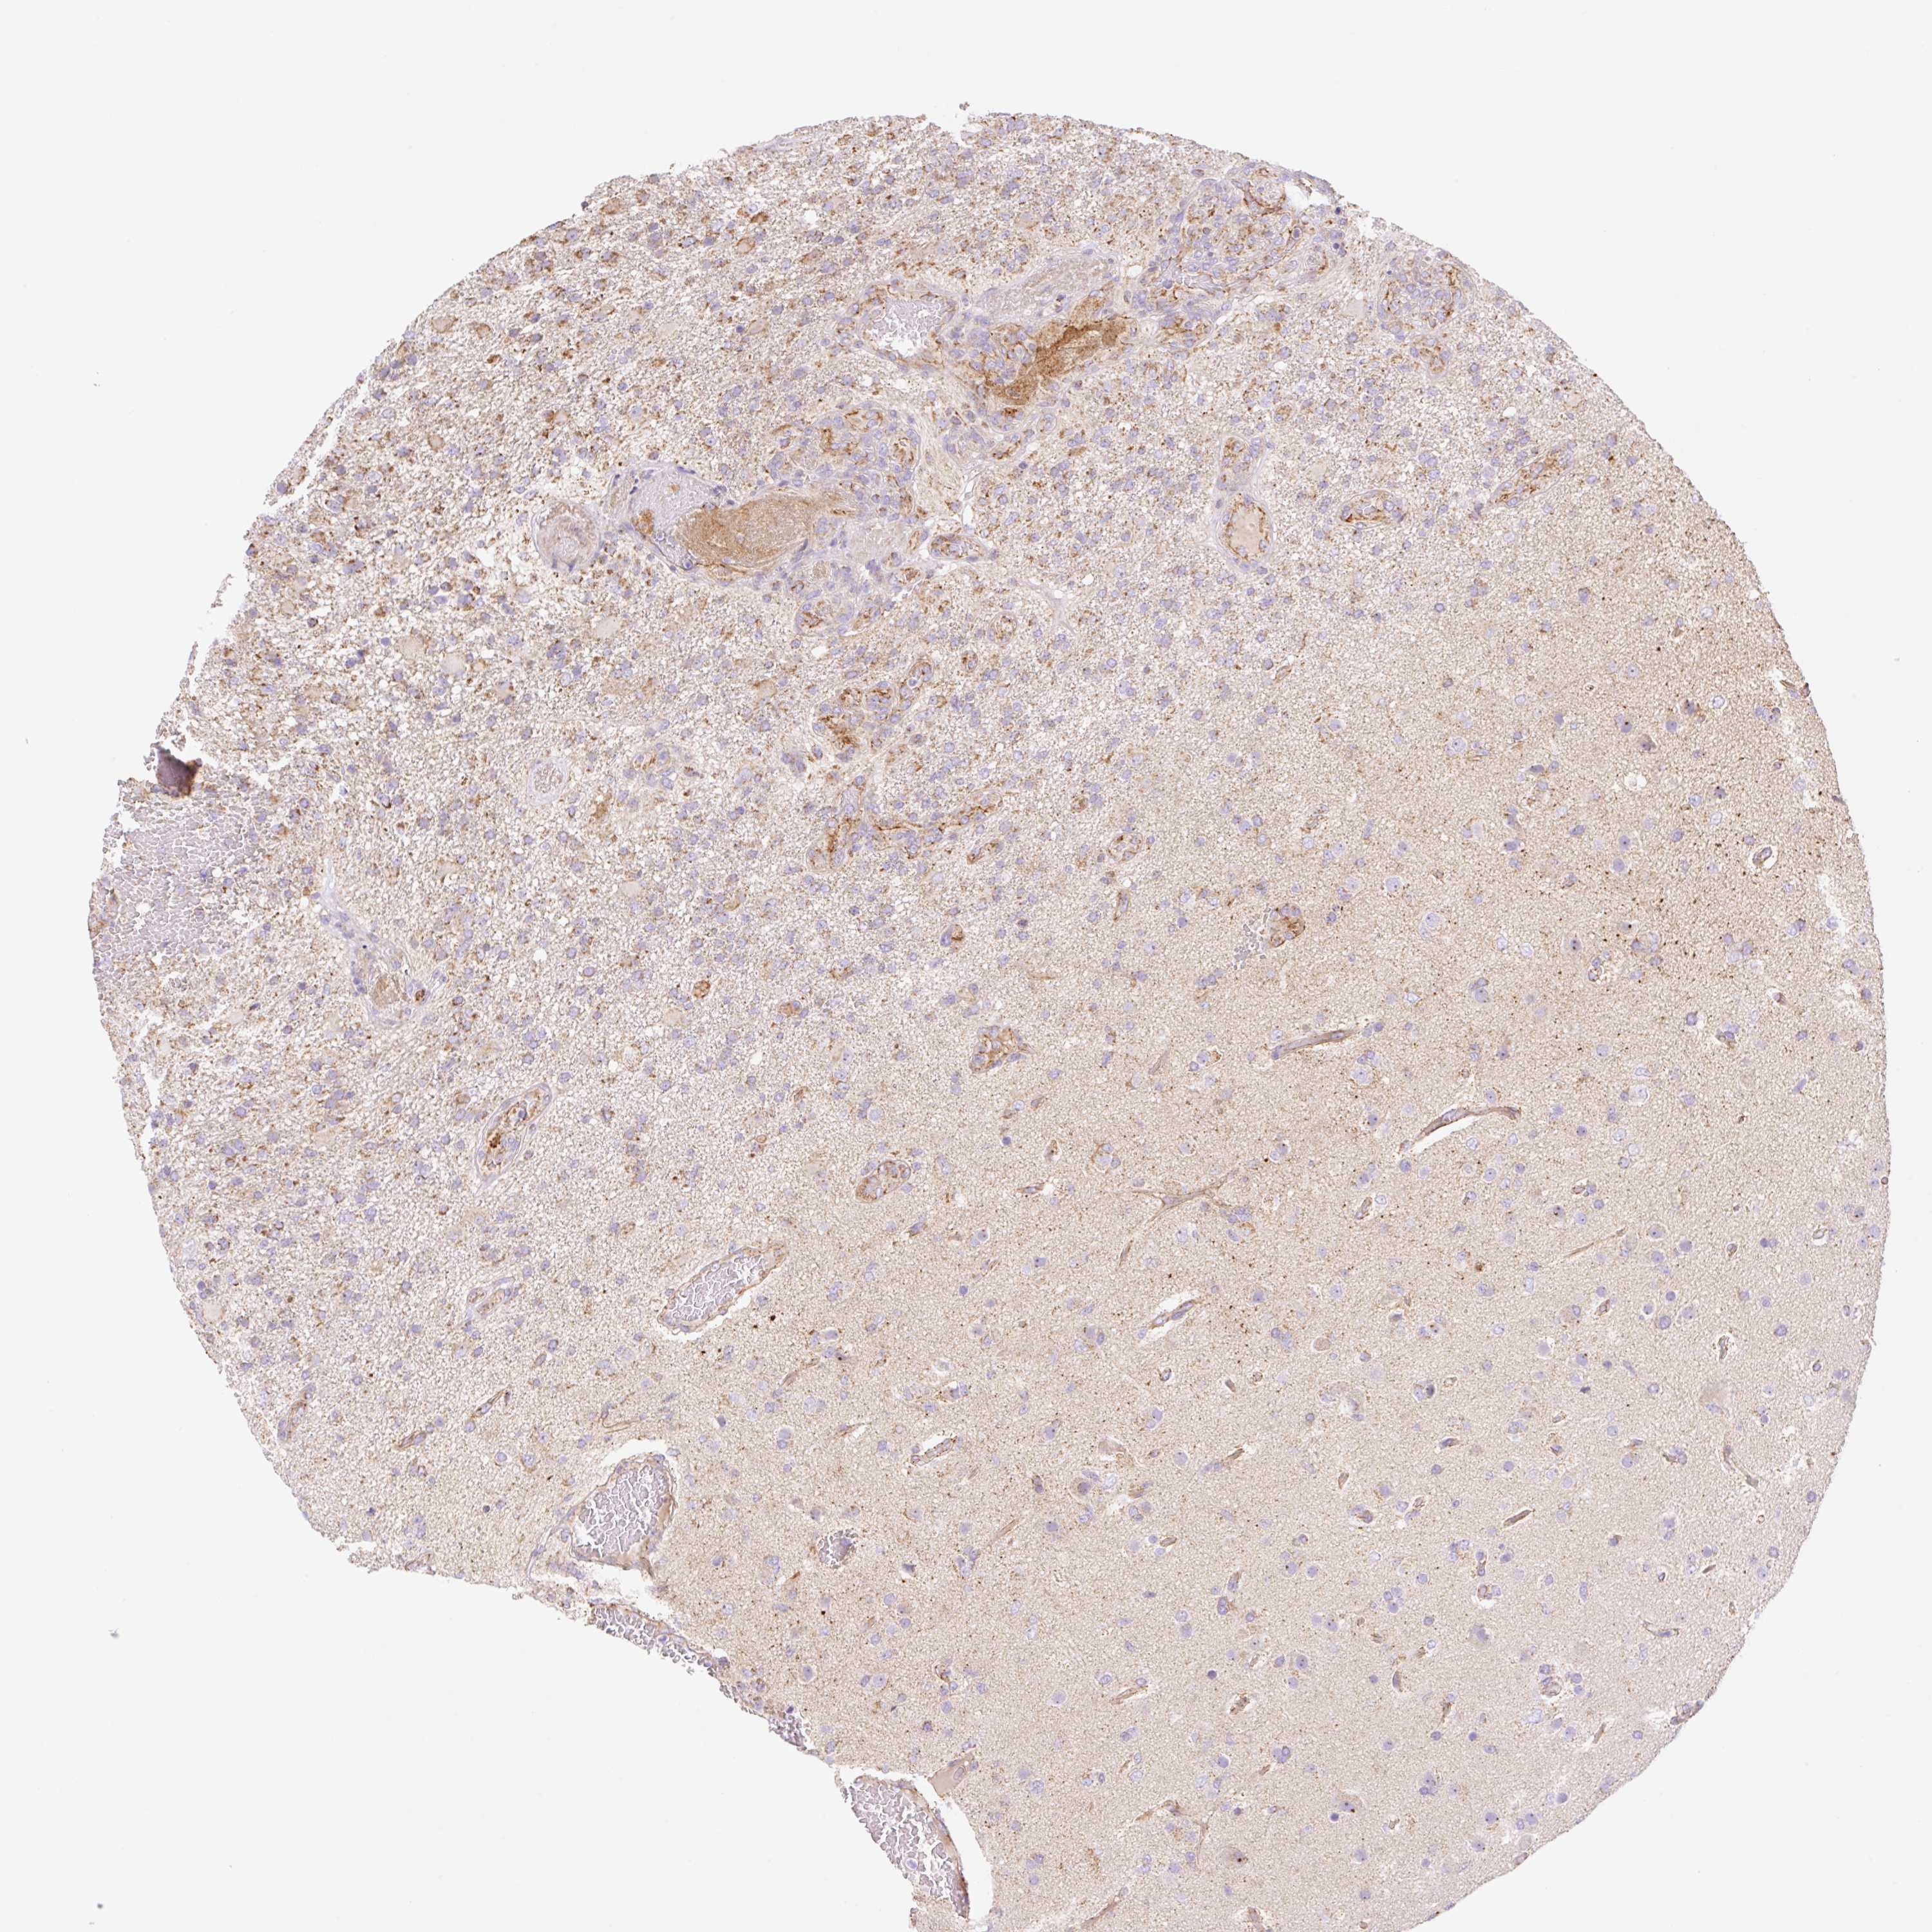

GLIOMA - Protein expressioni

A mouse-over function shows sample information and annotation data. Click on an image to view it in a full screen mode. Samples can be filtered based on level of antibody staining by selecting one or several of the following categories: high, medium, low and not detected. The assay and annotation is described here.

Note that samples used for immunohistochemistry by the Human Protein Atlas do not correspond to samples in the TCGA dataset.

Antibody stainingi

Antibody staining in the annotated cell types in the current human tissue is reported as not detected, low, medium, or high, based on conventional immunohistochemistry profiling in selected tissues. This score is based on the combination of the staining intensity and fraction of stained cells.

Each image is clickable and will lead to virtual microscopy that enables deeper exploration of all samples and also displays staining intensity scores, fraction scores and subcellular localization as well as patient and tissue information for each sample.

Antibody HPA056293

Staining

High

Medium

Low

Not detected

Intensity

Strong

Moderate

Weak

Negative

Quantity

>75%

75%-25%

<25%

None

Location

Nuclear

Cytoplasmic/membranous

Cytoplasmic/membranous,nuclear

Glioma, malignant, High grade